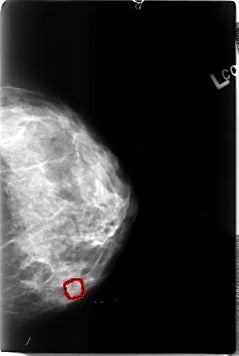

B_3033_1.LEFT_MLO

LEFT_MLO LINES 4544 PIXELS_PER_LINE 2992 BITS_PER_PIXEL 12 RESOLUTION 50 NON_OVERLAY

FILE: B_3033_1.LEFT_CC.OVERLAY

TOTAL_ABNORMALITIES 1

ABNORMALITY 1

LESION_TYPE MASS SHAPE IRREGULAR MARGINS OBSCURED-ILL_DEFINED

ASSESSMENT 3

SUBTLETY 2

PATHOLOGY MALIGNANT

TOTAL_OUTLINES 1

BOUNDARY